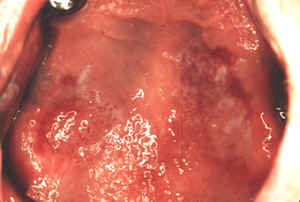

El paladar es un sitio raro pero puede ser involucrado en los pacientes con enfermedad severa.

Esta mujer padece una considerable  incomodidad  devido a un liquen erosivo.

El paciente también tiene diabetes mellitus, una enfermedad asociada a menudo con el  liquen plano. Estudios en un grupo de pacientes con  liquen plano  revelan que un 30% tienen alterada la curva de tolerancia a la glucosa.